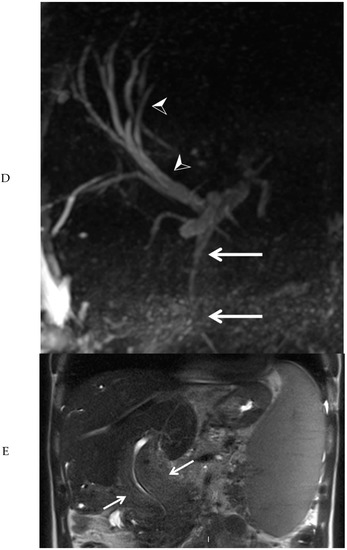

Subsequently, EUS combined with fine needle biopsy, and MRI of the upper abdomen were performed. EUS showed a highly vascular mass with a benign aspect. EUS-guided fine needle biopsy was somewhat difficult due to hardness of the mass. The histopathologic findings were most consistent with a lesion of vascular origin, such as hemangioma. MRI of the upper abdomen revealed a large mass surrounding the common bile duct, central intrahepatic bile ducts, cystic duct, and gallbladder, without diffusion restriction. After administration of intravenous contrast medium, no enhancement of the mass was visible in the arterial phase (Figure 3A). However, many small vessels were visible within the mass in the portal venous phase (Figure 3B), with diffuse homogeneous enhancement of the mass in the delayed phase (Figure 3C). At the MRCP, narrowing of the common bile duct was visible along its complete course, combined with dilation of the intrahepatic bile ducts (Figure 3D). At T2-weighted imaging, the mass around the narrowed common bile duct was slightly hyperintense when compared to the liver parenchyma (Figure 3E).

Figure 3. Magnetic resonance imaging of the mass in the upper abdomen (arrows). Shown are T1 weighted subtraction images of the mass in the upper abdomen with fat suppression after administration of intravenous contrast medium in the arterial (A), portal venous (B), and delayed phase (C). At magnetic resonance cholangiopancreaticography, narrowing of the common bile duct is visible along its complete course (arrows), combined with dilation of the intrahepatic bile ducts (arrowheads) (D). At T2-weighted imaging (E, coronal view), the mass surrounding the narrowed common bile duct was slightly hyperintense, when compared to the liver parenchyma (arrows).